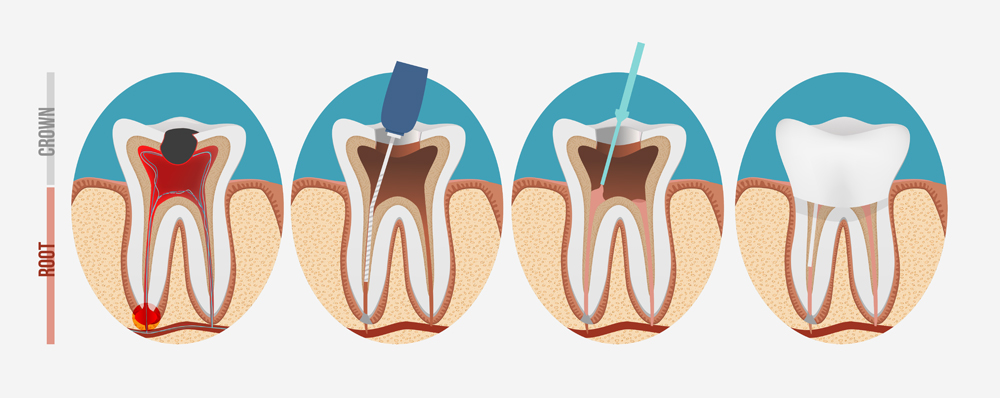

診査から根管治療前処置、根管治療、支台築造、歯冠修復までの一連の治療流れ

診査・診断・カウンセリング根管治療 を行なう歯の診査はいろいろあり、当院ではレントゲン撮影、CT撮影、触診、打診、神経の生活度の診査、歯周ポケット検査から歯の状態を診査します。個々の歯によって病気の状態は様々です。治療の難易度、予後、治療に伴うリスク、治療期間、費用などをご説明していきます。当院で治療を行う歯には、通常の二次元画像のレントゲンでは診断が難しい場合、または、治療にあたって歯根の形を詳細に把握し、根管の形に適したサイズの器具を選択するため、根管治療専用の高精細モードのCBCT 撮影を行うことがほとんです。 当院のCBCT は根管治療専用モードのため撮影範囲が最小です。インプラント用CTのような撮影範囲が大きい機種よりも被曝量が少なく、無駄な被曝がないよう配慮しています。 |

根管治療前処置根管治療に入る前におこなう治療で、歯の状態が詳しく把握できるとても重要なステップです。現在かぶっている、クラウン、インレー、コアやポストをはずし、その下の虫歯をチェックします。虫歯がある場合(が圧倒的に多いです)除去します。ひびの染め出しも必ずおこないます。その後、隔壁が必要な場合は隔壁をおこないます。 隔壁(かくへき)とは?虫歯等で削られてしまい歯がない部分に壁を作ることです。この壁の囲いが無いと、ラバーダムをしても唾液や血液が入りやく、ラバーダムをの意味がなくなってしまいます。また仮蓋も分厚くできません。 |

根管治療治療はラバーダムの装着を行い、根管治療中はマイクロスコープを常に使用した治療を行います。上の奥歯の治療ではよく見落とされている根管(MB2)があり、細菌の繁殖部位になり治らない原因になりますマイクロスープを使用しながら見逃されてしまった根管(MB2)を探索しているところMB2を発見し穴を広げたところ、殺菌がしっかり届くようになります |

支台築造(コア、ファイバーポスト+コア)殺菌をおこなった根管内に、ふたたび細菌が入らないようにするためのバリアとなる大切な治療です。当院では、なるべく感染の機会を与えないように全て直接法でおこなっております。現在一番良いとされている接着性の素材を用いております。非常に重要なステップですので、必ずラバーダム、マイクロスコープを使用して接着阻害因子を徹底的に排除しております。ほとんどの場合、根管充填と同日におこないます。 |

歯冠修復(かぶせものの治療)歯冠修復は、虫歯や処置で欠けた部分を詰めたり、被せたりする処置になります。 |

まずは神経を取るための麻酔をかけ、根管部分が見えるように歯の表面部分を削り、露出させます。

マイクロスコープを装着し、神経や歯髄、血管など根管部分にある組織はすべて細菌に感染しているため、ファイルという精密な針で全てを除去します。根管部分が枝分かれしている場合や曲がっている場合などは非常に処置の難易度が上がります。

もし、治療中に根管に破折(折れてしまっていて根管が破れている)あるいは穴が空いてていたなどの問題があれば、歯根端切除術や抜歯などの手術に切り替えることもあります。

根管内の感染部分を全て取り終えたら根管内をリーマーという専用器具で洗浄、消毒を行います。なんどか繰り返し、殺菌し終えたらゴム製のガッタパーチャという密閉性の高い薬剤で根管内を充填し感染部分の除去・消毒・充填・封鎖は終了です。

その後、削ってしまった部分にかぶせものをして元通りに見えるようにします。かぶせものも隙間ができないように細心の注意を払います。